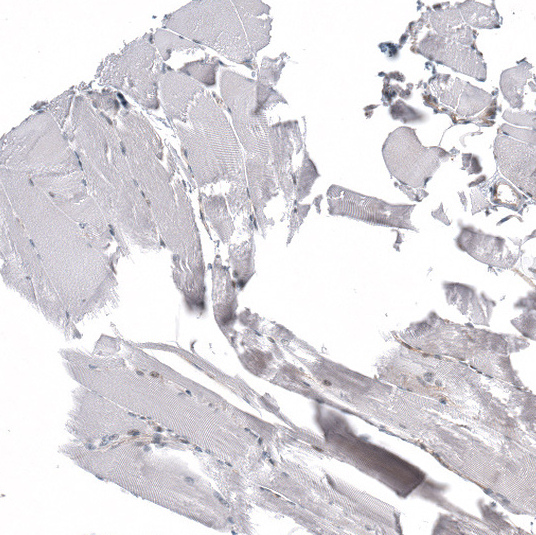

Immunohistochemical staining of human testis shows moderate nuclear positivity in cells in seminiferous ducts.